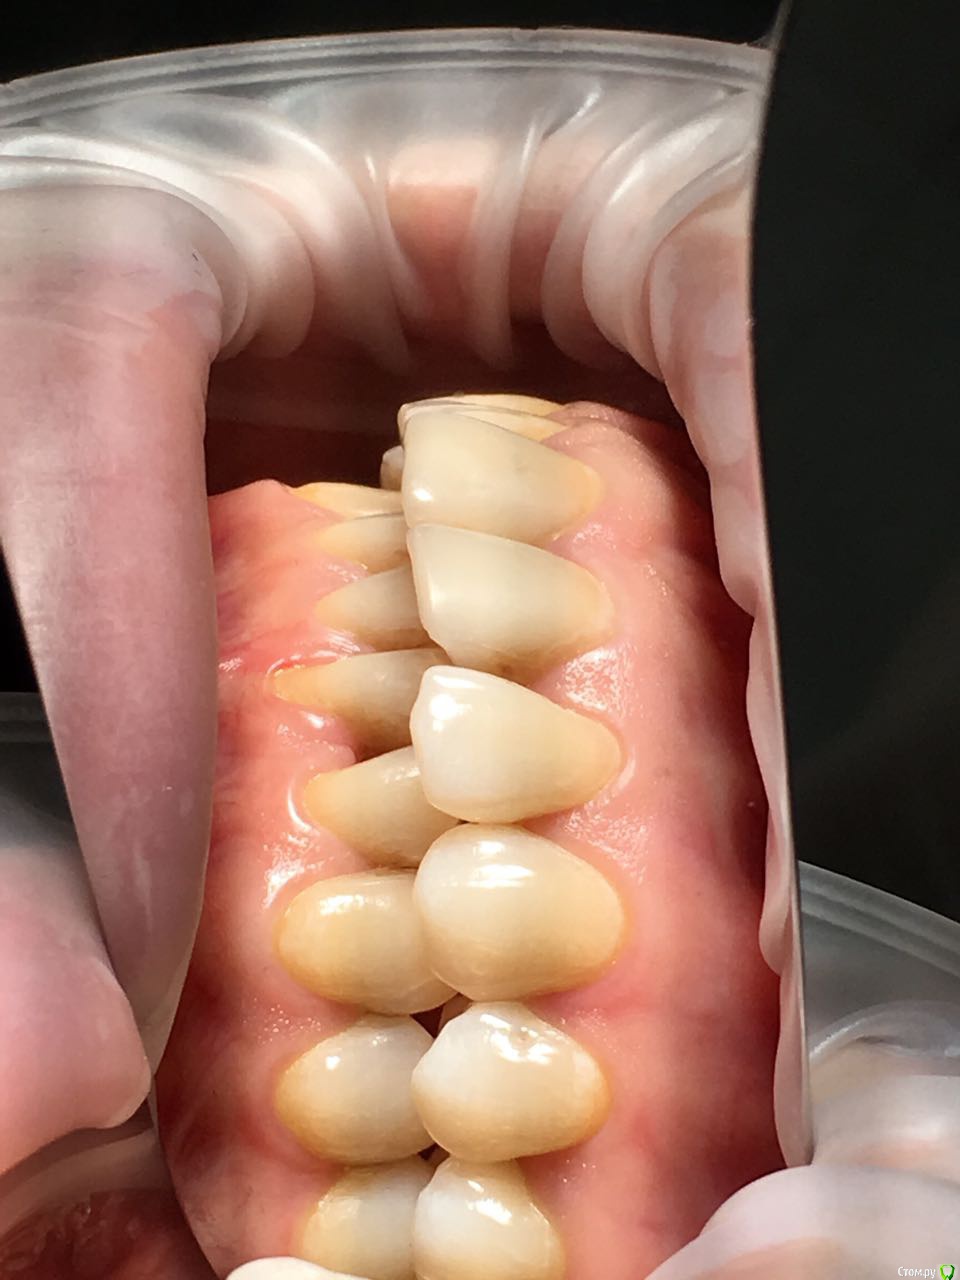

Kema Опубликовано 24 сентября, 2018 Автор Поделиться Опубликовано 24 сентября, 2018 Ещё фото Ссылка на комментарий

Kema Опубликовано 25 сентября, 2018 Автор Поделиться Опубликовано 25 сентября, 2018 У меня нет нижней правой шестёрки. Правая восьмёрка подвинула семёрку, семёрка наклонилась. Левая ретинированная восьмёрка удалена. На правой стороне жевать неудобно. Ещё верхние зубы наклонились вперёд. Начитавшись про ортогнатические операции хотела узнать показана ли мне она. Ссылка на комментарий